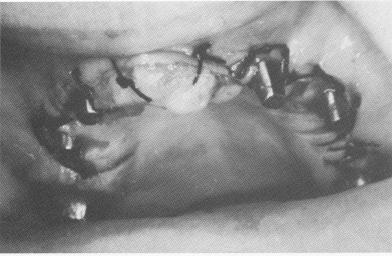

Fig. 11-130. The plaster index with the copings included.

3 Maxillary plaster index with copings included